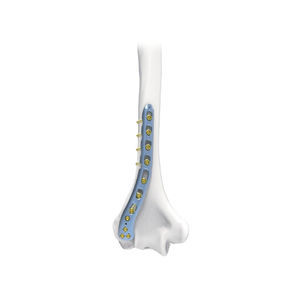

穴の数: 8, 16 unit

穴の直径: 2.7, 3.5 mm